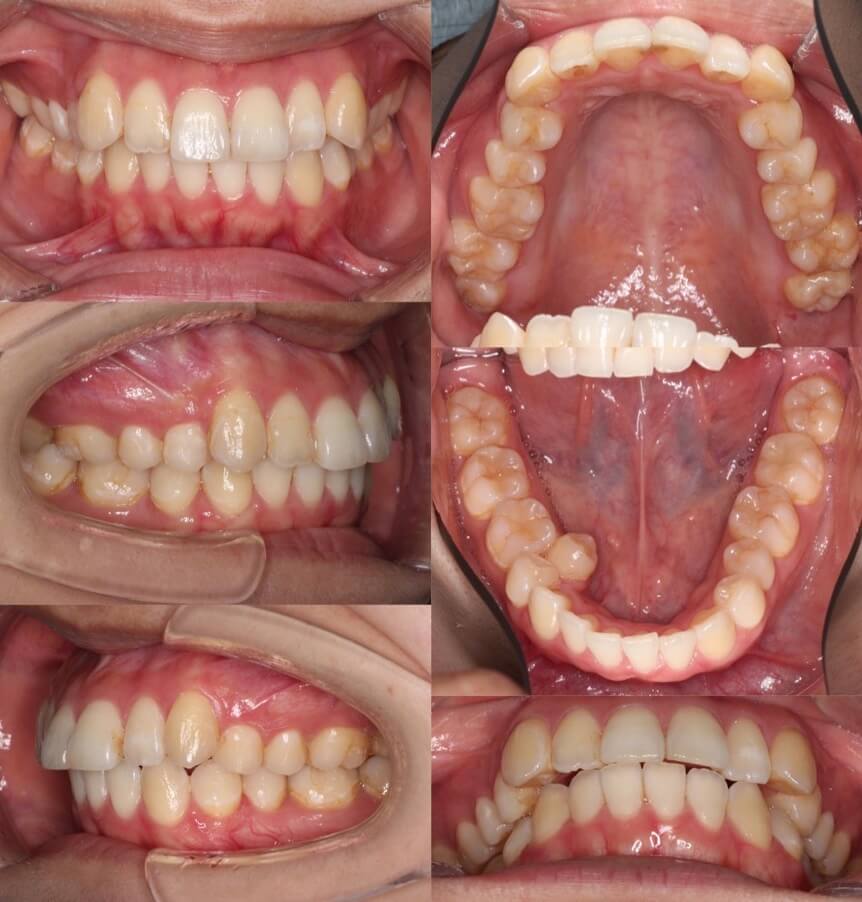

「開咬ならマウスピースも可能」

20代女性・マウスピース型装置・前歯傾斜型

マウスピース型矯正治療は前歯の歯根の後方移動が難しく、口ゴボ症例の適応症は少ないと言えます。その中で、開咬症例は数少ない適応症です。外開きになっている前歯を傾斜移動をコントロールしながら、後方移動させました。

<症例概要> 難易度:★★★★☆

主訴:口元の突出と前歯のかみ合わせ

年齢・性別:20代女性

住まい:千葉県八千代市

症状:開咬・上下顎前歯唇側傾斜・叢生

治療方針:抜歯空隙の閉鎖(中等度固定)

治療装置:マウスピース型矯正装置(アライナー装置)

抜歯:上下左右4番(計4本)

治療期間:2年1か月

アライナー枚数:29+27+20ステージ

リテーナー:上下クリアタイプ+フィックスタイプ

治療費用:990,000(税込)

代表的副作用:痛み・治療後の後戻り・歯根吸収・歯髄壊死・歯肉退縮